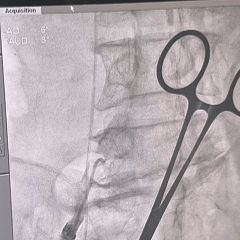

术中影像

8mm外周球囊扩张髂动脉狭窄处

根部造影可见大量反流

TF29瓣膜,0位初始定位

全展开造影,大弯侧位置尚可

左侧位造影,小弯侧位置偏深

回收后调整瓣膜释放位置

全展开造影,瓣膜位置较高

多体位造影,瓣膜位于瓣上

再次回收,第三次释放

全展开造影,大弯侧0位

左侧位造影,小弯侧深度可

脱钩后造影,瓣膜位置可

外周血管检查,无损伤